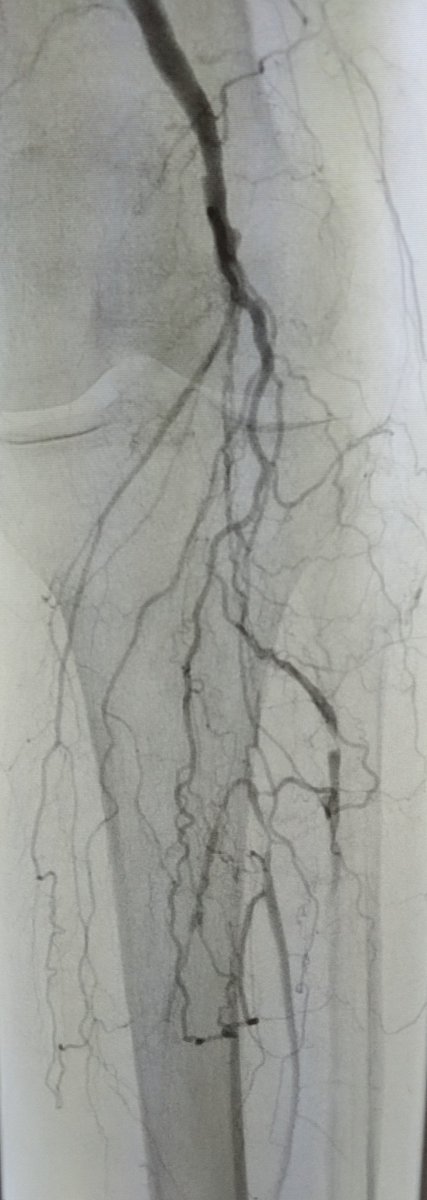

@ColoradoIR #CLIFighters Non-healing wound d/t inflow disease. Re-entry leads to ABI improvement from 0.4 to 1 and 2+ DP. @CLI_Global @kmadass @SDhandMD @KMSchramm @UCD_IR #stopthechop #mylegmylife